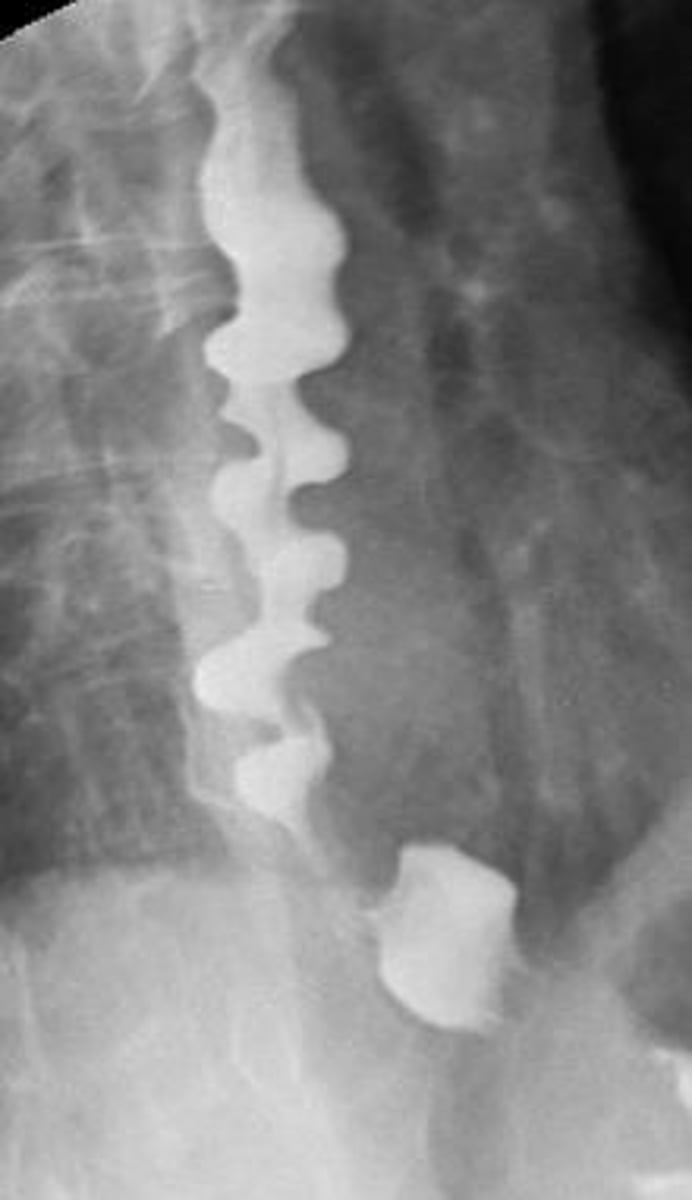

if a pt presents with severe retrosternal chest pain following large meals/rapid eating and intermittent dysphagia, what would you expect to see on barium esophagram? What is the first line tx?

diffuse esophageal spasm → "corkscrew" on barium study

tx with PPIs

(sublingual nitro/CCB for spasms but may increase GERD sx)